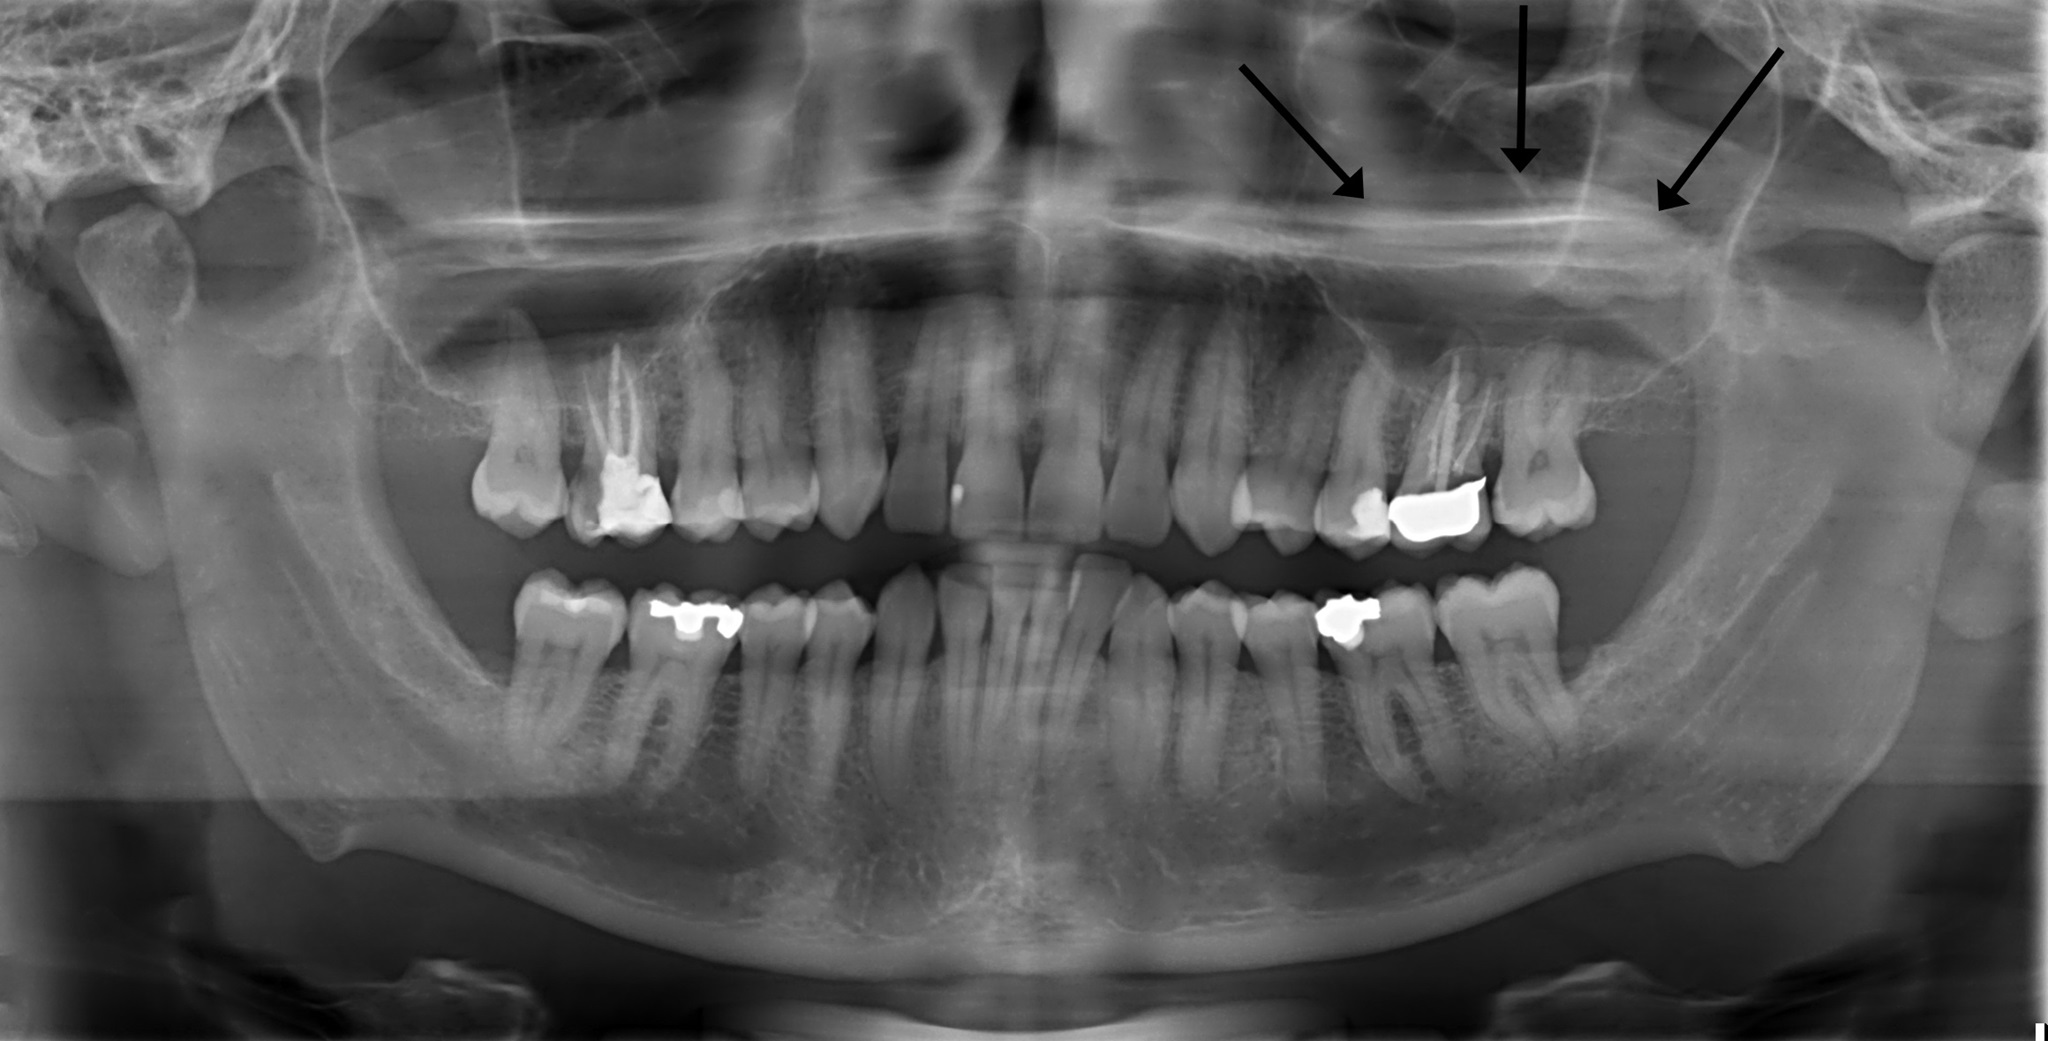

Kieferhöhlen Zyste

In manchen Fällen entstehen Zysten in der Kieferhöhle.

Diese sind meistens harmlos, allerdings muss man diese in manchen Fällen auch entfernen.